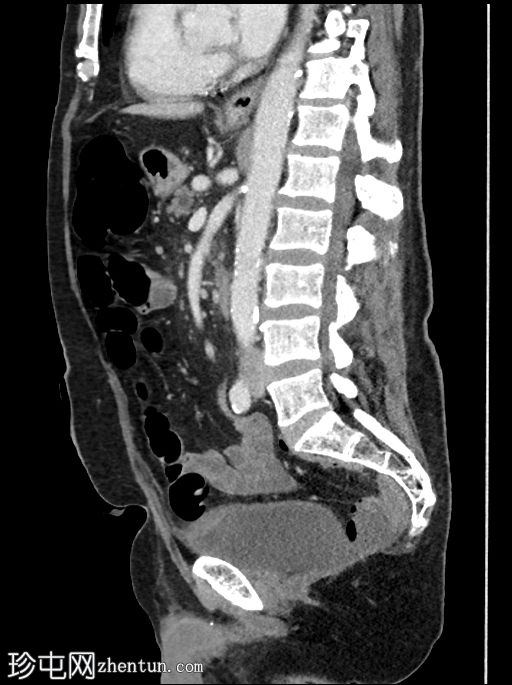

矢状位增强扫描(门静脉期)

可见胆道支架位置良好,管腔内可见分层气液平面。支架远端位于充满液体的D2段内。支架内未见明显放射性结石。

肝内胆管未扩张,但可见胆道积气。

胰头水肿,伴胰周脂肪浸润。未见明显积液。

胰头局灶性结节(代表已知的肿瘤),伴有上游主胰管扩张,位于萎缩的胰颈、胰体和胰尾内。背景可见胰腺实质内钙化。